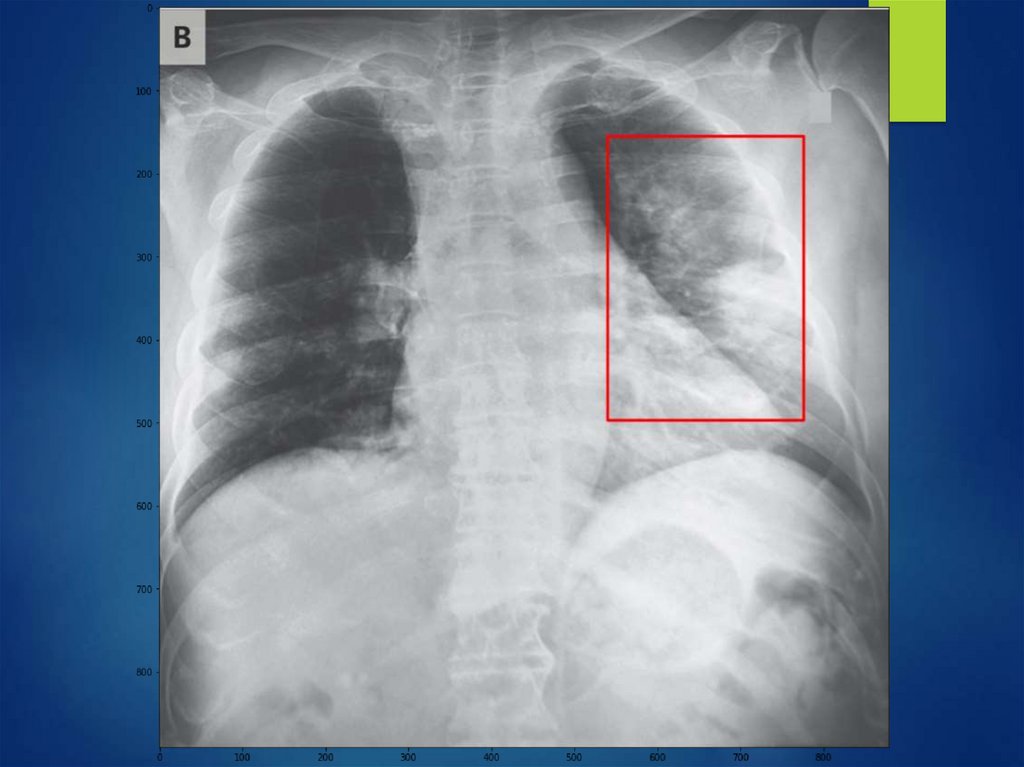

ОБОБЩЕННОЕ ПОНЯТИЕ ЛЕГОЧНОЙ

ДИССЕМИНАЦИИ